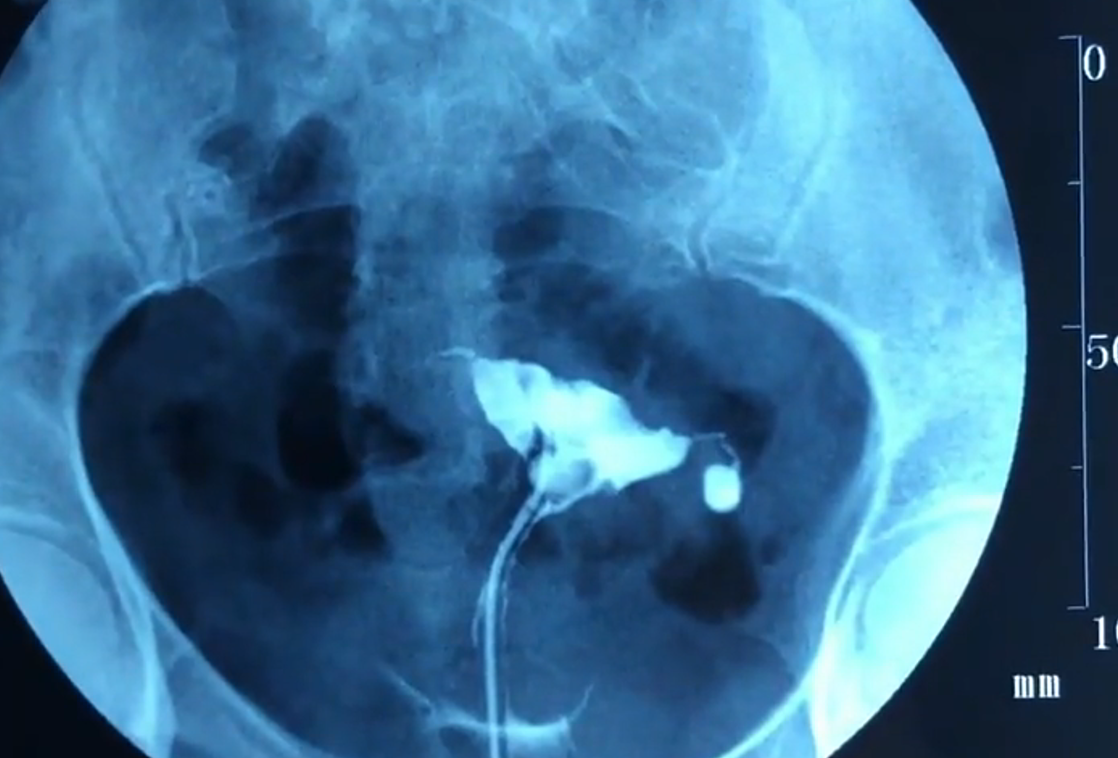

您好输卵管的情况目前最好的诊断方法就是数字化动态输卵管碘油造影,该技术除对不育症有诊断意义外还具有一定的治疗意义,它是通过乳胶双腔管向子宫持续贯注造影剂,动态的观察子宫输卵管和盆腔影像,患者可在第一时间看到自己的宫腔和输卵管情况,而且有录像电子图片保存祝你健康1检查操作经x线。

动态的观察子宫输卵管和盆腔影像,患者可在第一时间看到自己的宫腔和输卵管情况,而且有录像电子图片保存所以你只要选择专业的医院做是不会有太大痛感的输卵管阻塞的治疗1先要控制炎症,再做输卵管碘油造影,确定堵塞的具体部位和程度,据此选择具体的复通方案每种复通方法都具有检查和疏通的作用。

输卵管堵塞表现为腹部不适月经不调痛经不孕性交疼痛胃肠道障碍乏力白带量的加多等 本病主要由输卵管炎症引起,阴道炎宫颈炎子宫内膜炎卵巢疾病阑尾炎结核病的病原菌上行感染等都是诱发因素 症状 影像学检查 经X线的子宫输卵管造影术可从荧光屏和X光照片上看到子宫腔的。